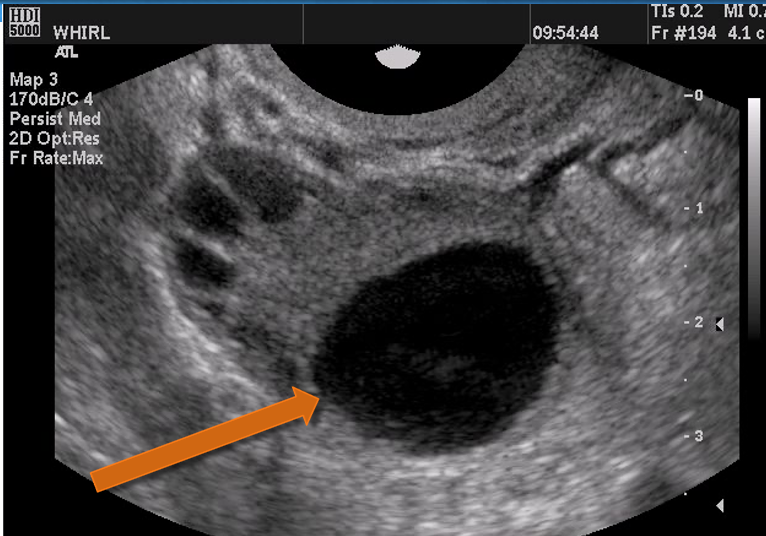

Reconnaître le follicule dominant à l’échographie